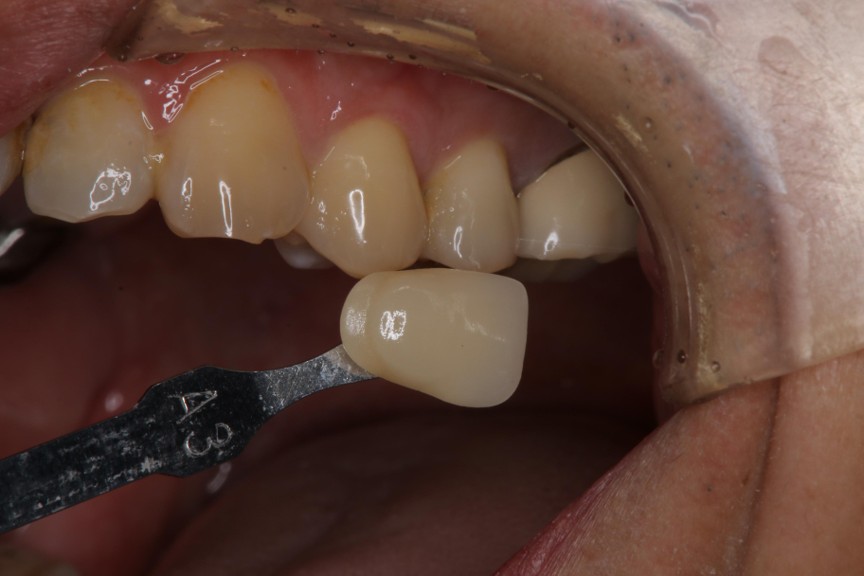

照相比色